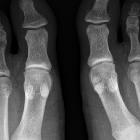

Geteiltes

Sesambein Os-metatarsale-I-Köpfchen medial, ein häufiger, nicht pathologischer Befund.